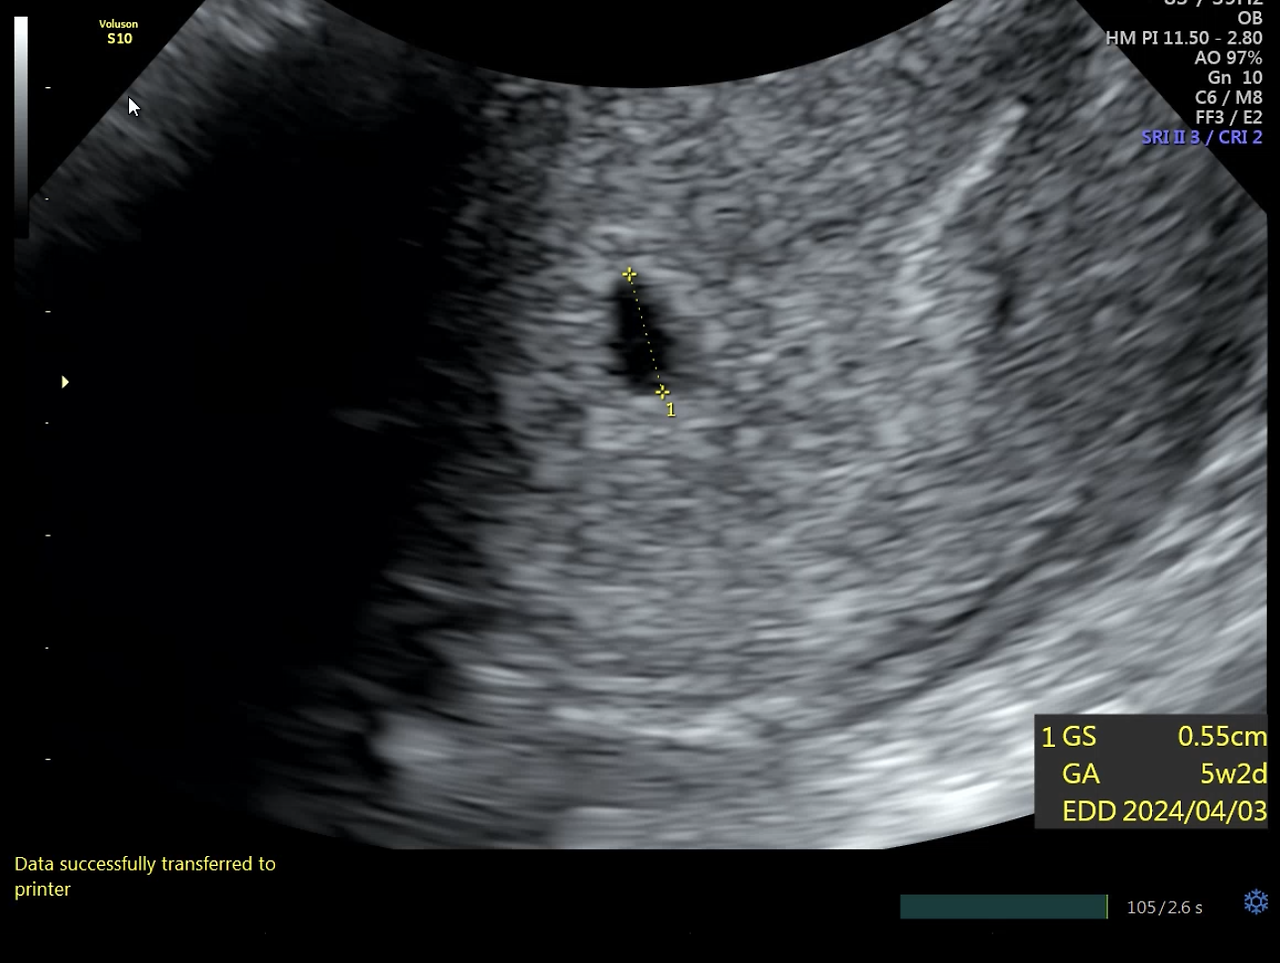

한국으로 돌아오자 마자 산부인과에서 검진을 받고 임신 사실 확인서를 받게 되었다.

아기집을 확인하고 나니 비로소 실감이 난다.